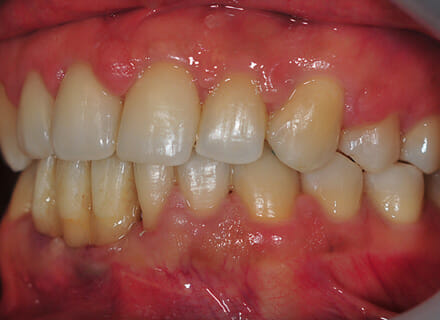

This patient came to us with 2 big issues: he had a number of failing teeth in the lower jaw at the front. Due to gum (periodontal) disease these teeth had come loose and started to grow apart splaying out in all directions. In the upper jaw the teeth had also started moving so that big gaps had appeared between them. We treated the gum disease to save most of the teeth and placed 2 implants in the lower jaw, placing 4 new teeth on top of them immediately (immediate dental implant treatment).

He then went to see Charlene who does our braces (orthodontics) and she placed some tooth coloured brackets. The braces pulled all the teeth together and levelled them off. Finally we fitted new ceramic implant bridge teeth to replace the lower temporary teeth we fitted initially.